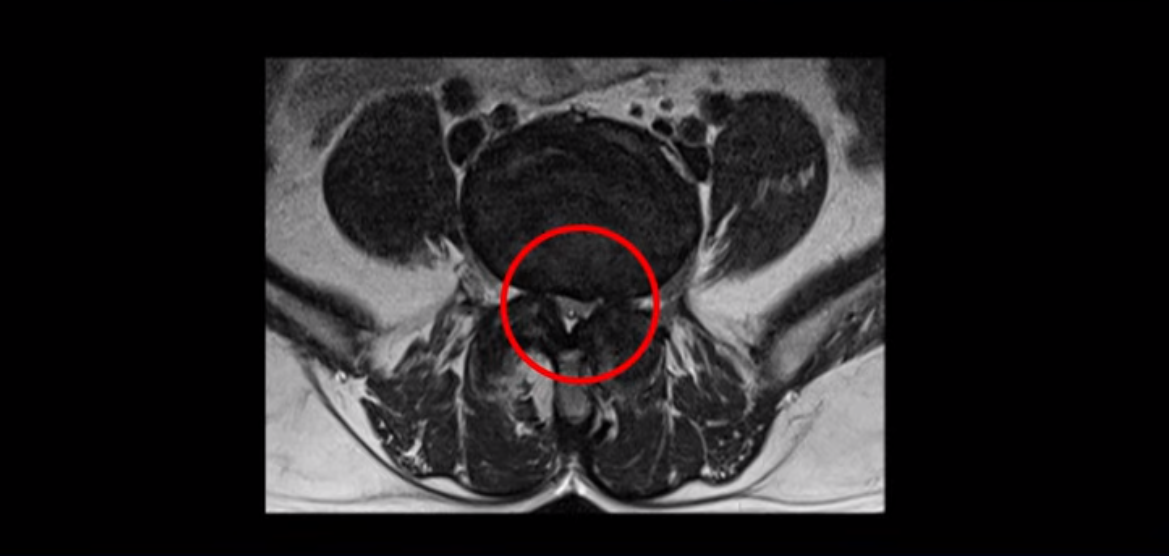

단면으로 보면 왼쪽 후궁을 제거한 흔적이 보입니다.

5번 1번도 왼쪽 후궁을 열고 수술 받았습니다.

하지만 중심성 협착은 여전히 심한 상태입니다.

이분은 오른쪽, 왼쪽 다리에 모두 방사통이 심하고 왼쪽 다리에 마비 증상, 즉 풋드랍(족하수) 증상이 있습니다. 왼쪽 신경 가지가 빠져나가는 추간공을 보면 두 마디가 좁아져 있습니다.

이런 신경 구멍이 좁아져 있는 걸 협착이라고 합니다.